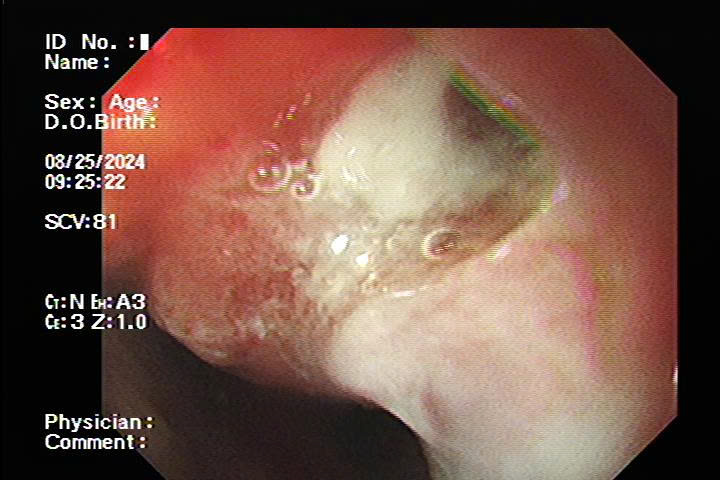

Nội soi tiêu hóa là kỹ thuật sử dụng ống nội soi mềm có gắn camera để kiểm tra trực tiếp bên trong thực quản, dạ dày và đại tràng. Phương pháp này giúp bác sĩ quan sát rõ cấu trúc niêm mạc, phát hiện tổn thương, chẩn đoán chính xác các bệnh lý tiêu hóa.

Bác sĩ đưa ống nội soi vào cơ thể để kiểm tra tình trạng đường tiêu hóa, có thể kết hợp sinh thiết khi cần thiết.

Dựa vào hình ảnh thu được, bác sĩ sẽ đưa ra chẩn đoán và kế hoạch điều trị phù hợp.

- Hình ảnh nội soi sắc nét giúp bác sĩ đưa ra chẩn đoán chính xác hơn so với phương pháp chụp X-quang.